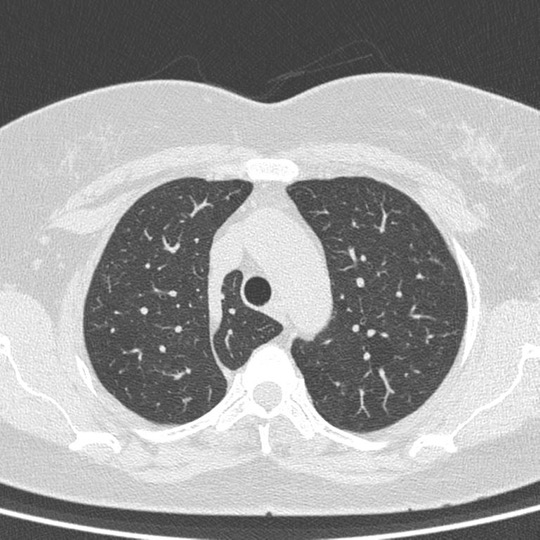

An Azygos lobe fissure is seen on right side. It extends from the lateral aspect of the vertebral body posteriorly, to the right brachiocephalicvein and SVC anteriorly.